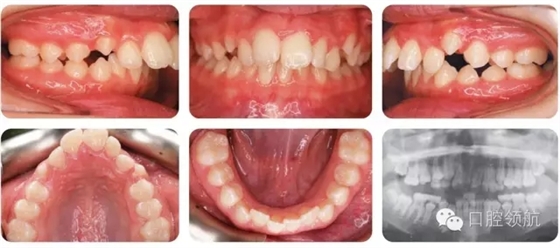

12歲的女性患者,由全科牙醫(yī)轉(zhuǎn)診。該患者健康情況良好,主訴是前牙前突(圖2.1)。

圖2.1

口內(nèi)相中的牙列處于哪一階段?

早期恒牙列。除LL7部分萌出以外,其余第二磨牙尚未萌出。

錯(cuò)牙合的主要特點(diǎn)有哪些?

● 安氏II類(lèi)1分類(lèi),深覆蓋,深覆牙合,下前牙咬在上前牙腭側(cè)黏膜。

● 右側(cè)磨牙1/2牙尖Ⅱ類(lèi)關(guān)系,左側(cè)磨牙I類(lèi)關(guān)系。

● 中線一致。

● UL2多生牙已萌出。